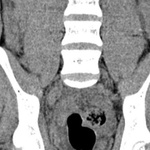

Trong vòng 20 phút, anh được đưa đến Bệnh viện đa khoa Xuyên Á, tại khoa cấp cứu, bác sĩ ghi nhận huyết áp 200/100mmHg, nghi ngờ đột quỵ, lập tức chỉ định chụp MRI và phát hiện vùng nhồi máu tiểu não phải.

Bệnh nhân được tiêm thuốc tiêu sợi huyết qua đường tĩnh mạch, giúp tái thông mạch máu bị tắc nghẽn. Chỉ sau ít phút, anh B. đã giảm chóng mặt, phục hồi thăng bằng và đi lại được.